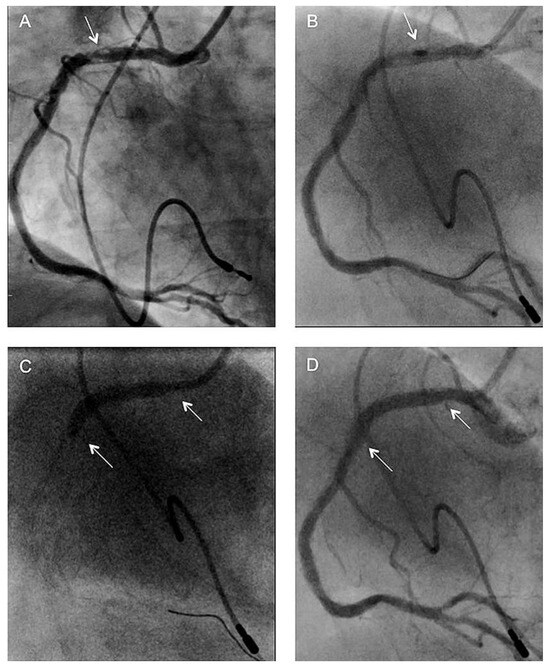

6 pages, 1978 KB

Article

Complex Percutaneous Coronary Interventions by Transradial Approach Using Sheathless Guiding Catheters

by Stephane Noble, Robert Francis Bonvini, Caroline Frangos, Pierre-Frédéric Keller and Marco Roffi

Cardiovasc. Med. 2012, 15(7), 218; https://doi.org/10.4414/cvm.2012.01682 - 29 Aug 2012

Cited by 1 | Viewed by 95

Abstract

Objective: To analyse our single centre experience with sheathless guiding catheters (GC) for complex percutaneous coronary interventions (PCI). Background: Failure of performing transradial approach (TRA) increases with the sheath size used, especially in cases of small and tortuous radial arteries. The [...] Read more.

Objective: To analyse our single centre experience with sheathless guiding catheters (GC) for complex percutaneous coronary interventions (PCI). Background: Failure of performing transradial approach (TRA) increases with the sheath size used, especially in cases of small and tortuous radial arteries. The use of recently developed sheathless GC may facilitate performance of TRA for complex PCI requiring large-lumen GC. Methods and results: We retrospectively analysed 20 consecutive patients who underwent complex PCI performed by TRA with a Sheathless Eaucath® GC (Asahi Intecc, Japan). The patients mean age was 68.9 ± 11.3 years. Indications for PCI were ST elevated myocardial infarction in 2 patients (10%), acute coronary syndrome in 4 (20%), and chronic stable angina in 14 (70%). Right TRA was used in all but one case. The 7.5-French (F) sheathless GC was used in all the procedures. Radial and brachial arteries crossing was possible in all cases with no associated procedural or GC-related complications. The number of vessels treated per patient was 1.30 ± 0.47 with 1.70 ± 0.92 stents implanted per vessel. The left main stem was the treated lesion in 9 patients (45%), 5 patients (25%) had complex bifurcation lesions and one (5%) had chronic total occlusion. The remaining 5 patients (25%) had severely tortuous and/or calcified coronary lesions. Rotablation was required in 2 procedures. Mean fluoroscopic time was 20.3 ± 7.5 min and mean volume of contrast media was 254 ± 83 ml. Conclusion: This preliminary experience in complex PCI, suggests that TRA using 7.5-F sheathless GC might be an attractive alternative to transfemoral access using 7-F conventional. Full article

Show Figures

Figure 1